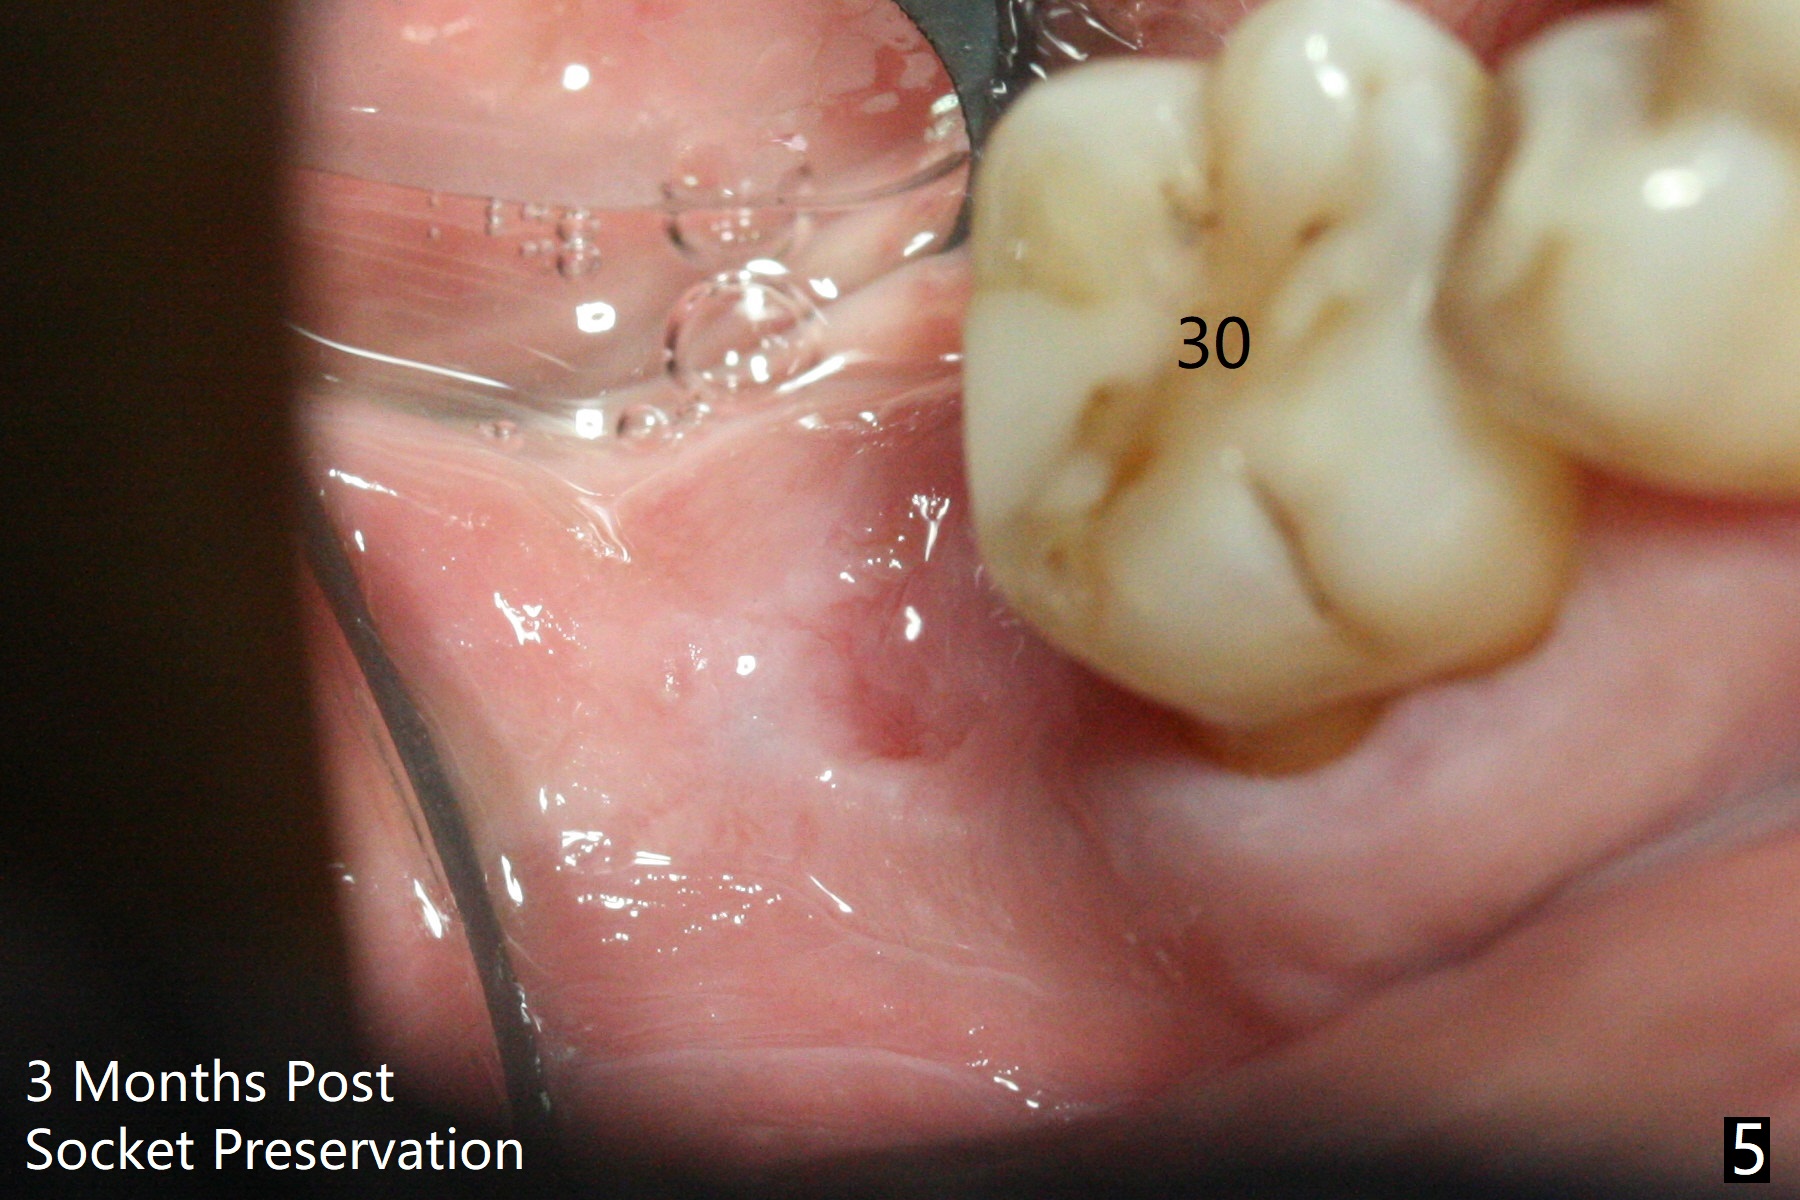

The socket shrinks with buccal plate reduction 3 months post socket preservation (Fig.5), as compared to 10 days postop (Fig.4). To restore the socket as much as possible, Magic Split is used (flapless), followed by Magic Expanders 3-3.8 mm for 11 mm (gingival level) and a 4x11mm dummy implant (Fig.6). The osteotomy is moved distal by using Lindamann bur; following 3.8 mm Magic Drill, a 4.5x11 mm dummy implant (Fig.7). Finally a definitive 5.5x9 mm implant is placed with <45 Ncm; a 6x2 mm healing abutment is placed to close the access (Fig.8). Autogenous bone harvested from the Magic Drill returns to the osteotomy mainly buccal prior to implant placement (Fig.8 *). The patient reports no discomfort immediately postop, thanks to the flapless technique. The patient has had postop pain; 11 days postop, the abutment and implant are found to be loose. After re-tightening by hand, the complex is seated deeper and more stable (Fig.9 arrow).